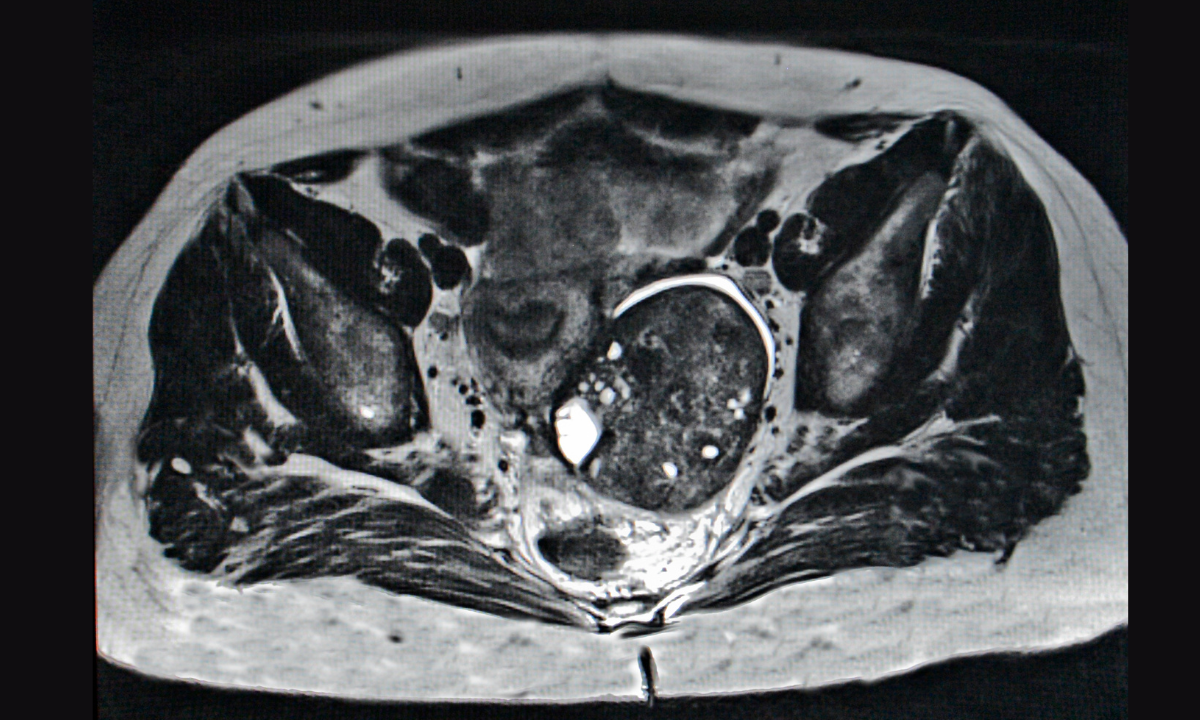

MRI uses strong magnets and radio waves to create highly detailed images of the pelvic area. This helps your doctor see soft tissues clearly and identify whether an ovarian mass is likely benign or cancerous. MRI is especially good at distinguishing between dermoid cysts, endometriotic cysts, and fibroids, which can sometimes appear suspicious on ultrasound.

Types of MRI images used

Your MRI scan uses several imaging techniques to build a complete picture:

T1-weighted images:

Show fat or blood inside a mass.

T2-weighted images:

Highlight internal structures and fluid content.

Contrast-enhanced images:

Use a contrast dye to make details like nodules and dividing walls easier to see.

Diffusion-weighted imaging (DWI):

Tracks how water moves within tissues to help detect abnormal cell growth.

MRI offers more detailed information than an ultrasound. It produces clear images that help doctors assess the nature of an ovarian mass and see if the cancer has spread beyond the ovaries.

The scan shows details about the tissue structure and whether the mass is solid or fluid-filled. For instance, functional cysts typically appear as fluid-filled areas with little to no solid tissue. These distinctions help your doctor decide whether surgery or simple monitoring is the best approach.